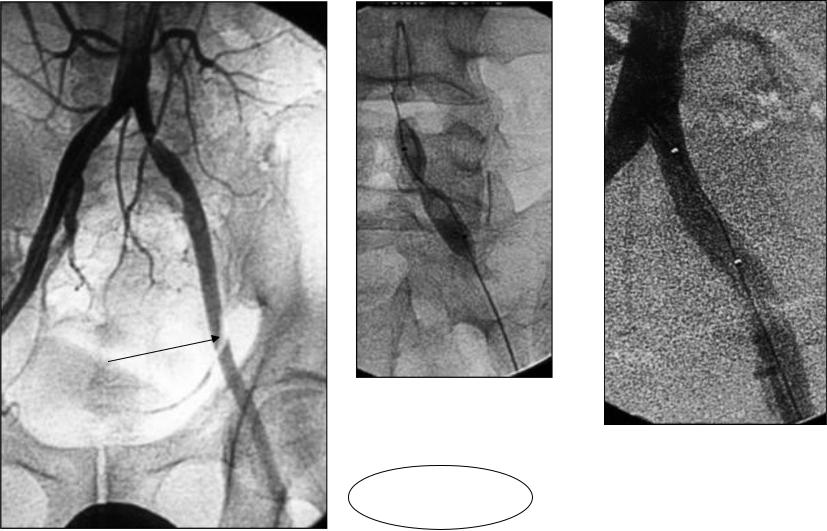

Дегенеративная LSS анатомически может включать центральный канал, латеральное углубление, отверстия или любую комбинацию этих мест (). Стеноз центрального канала может быть результатом уменьшения переднезаднего, поперечного или комбинированного диаметра вследствие потери высоты диска с выпуклостью межпозвонкового диска или без него, а также гипертрофией фасеточных суставов и желтой связки.Фиброз является основной причиной гипертрофии желтой связки и вызван накоплением механических нагрузок, особенно вдоль дорсальной части желтой связки. Трансформирующий фактор роста (TGF) -β, высвобождаемый эндотелиальными клетками, может стимулировать фиброз, особенно на ранней стадии гипертрофии. (11) Те же процессы, уменьшение высоты диска, гипертрофия фасеточного сустава (со спондилолистезом или без него) и / или замыкательная пластинка позвонка. остеофития также может привести к стенозу бокового углубления.Фораминальный стеноз может быть переднезадним в результате сочетания сужения дискового пространства и разрастания структур, расположенных кпереди от капсулы фасеточного сустава, и / или вертикальным в результате выступающих в отверстие заднебоковых остеофитов замыкательных пластинок позвонков вместе с фиброзом латерально выпуклого кольца или грыжи. диск, который прижимает нервный корешок к верхней ножке. (12) Фораминальный стеноз чаще затрагивает нервный корешок L5, так как отверстие L5-S1 имеет меньшее отношение площади отверстия к площади корня.(12)

Поясничные позвонки. Возможные области контакта с нервными корешками, как описано Jenis (12): 1 центральный; 2 боковые выемки; 3 отверстия; 4 экстрафораминальный